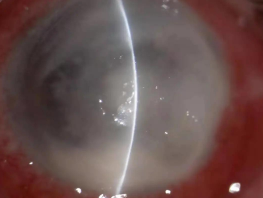

真菌性角膜炎是一種由致病真菌引起的、致盲率極高的感染性角膜病。常見(jiàn)的致病菌為曲霉菌,其次為鐮刀菌、白色念珠菌、頭芽胞菌及鏈絲菌等??沙霈F(xiàn)免疫環(huán)、衛(wèi)星灶、偽足、菌絲苔被、前方積膿及內(nèi)皮斑。